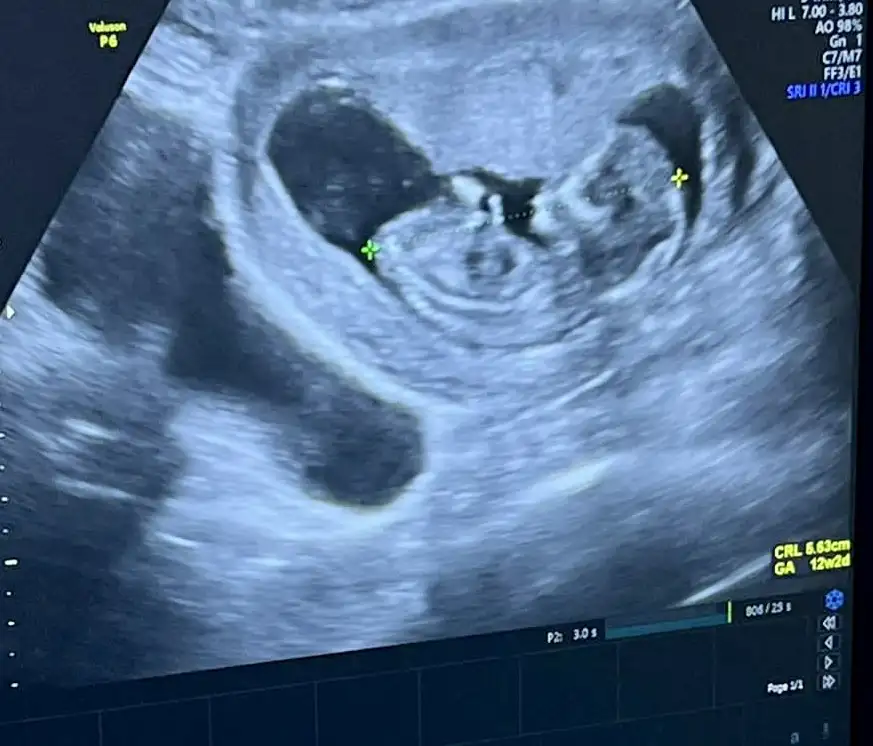

Kızlar banada tahminde bulunurmusunuz 12+5

Çok dikkatli şekilde baktım. Sivri çene için her ne kadar kız deseler de, nub hafiften yukarı bakıyor ve bu da erkek olduğunu gösteriyor. Sivri çene olup erkek olanını da görünce çeneye göre yorumlamak sanırım mantıklı gelmiyor bir yerden sonra, ama kız çıkarsa da nub belki pozisyonundan ötürü hafiften yukarı doğru bakıyormuş gibi çıkmış olabilir. Fakat ben yinede bebeğinizin erkek olduğunu düşünüyorum çünkü gerçekten de nub yukarı bakıyor.